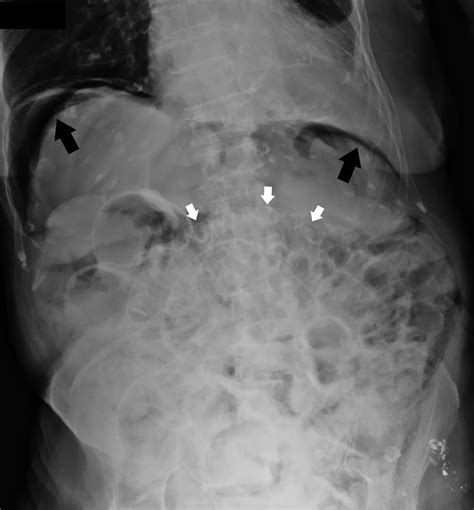

Abdominal X-ray Can show radiolucent areas along the bowel wall, but lacks sensitivity.

When reviewing imaging, radiologists look for the specific appearance of "bubbly" gas collections along the serosal or submucosal surfaces. Differentiating these cysts from free air (pneumoperitoneum) is the most critical step for the radiologist to ensure the patient is not facing a surgical emergency.